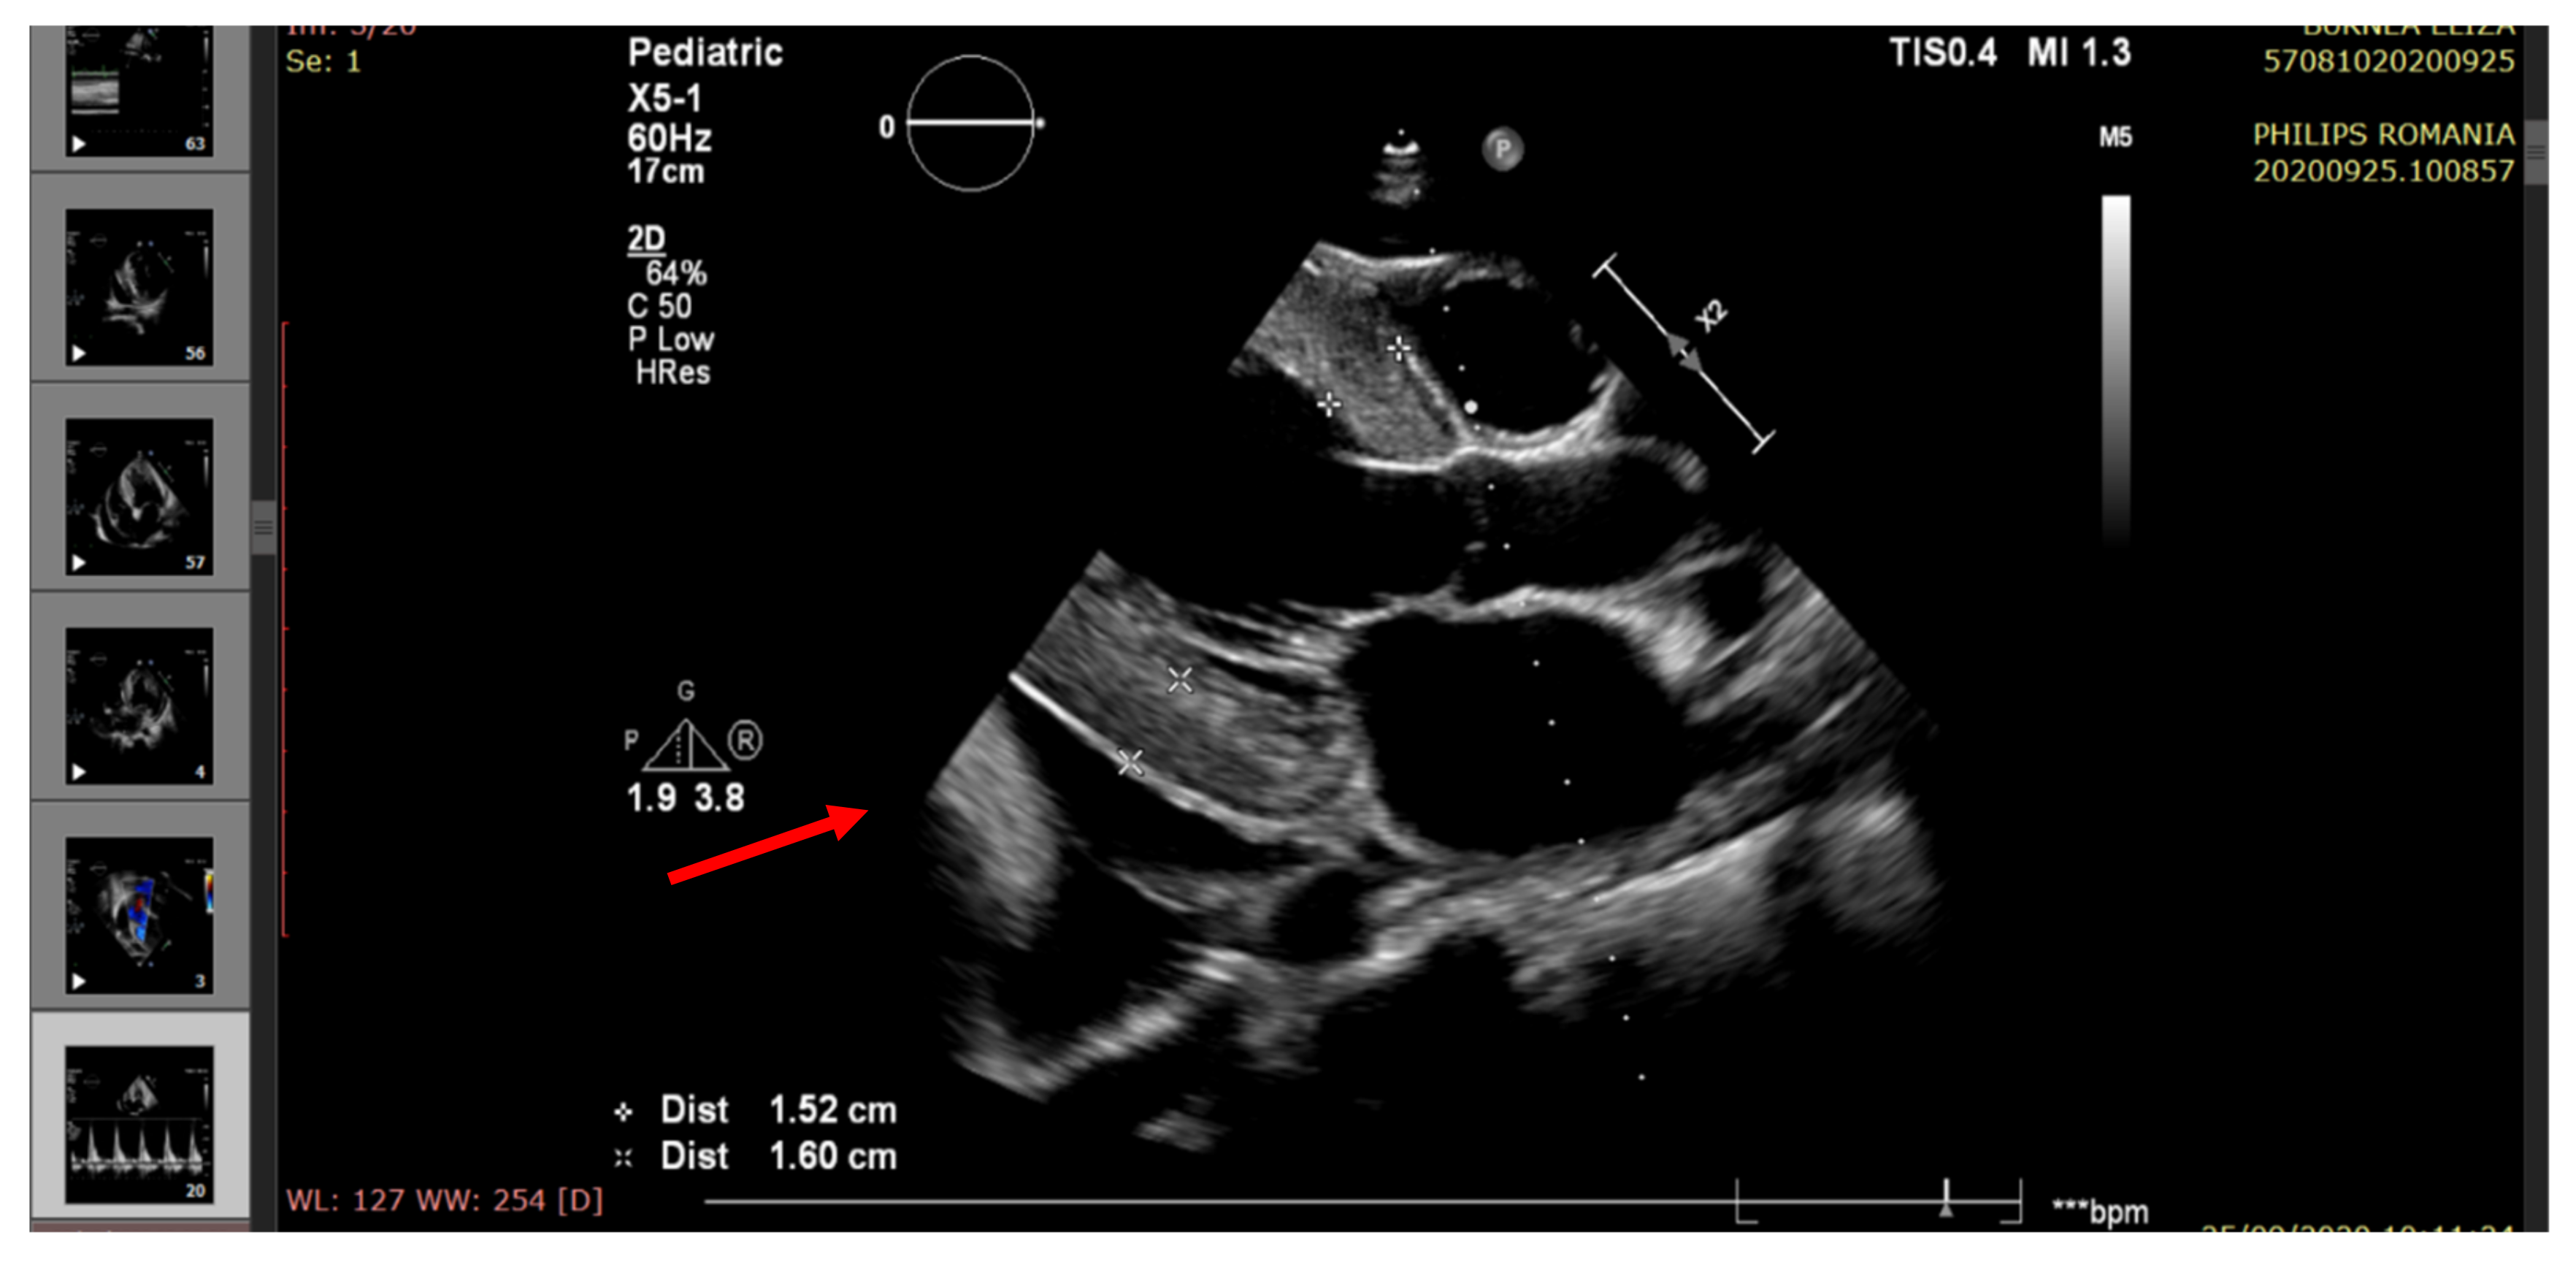

| Mitral annular plane systolic excursion (MAPSE) (mm) (M-mode) | 16.4 ± 2.4 | 15 | 9.2 | 12.2 | 8.3 |

| Pericardial fluid (edge) | <5 mm | Small (6 mm) | Raised (20 mm) | Moderate (14 mm) | Large (22 mm) |